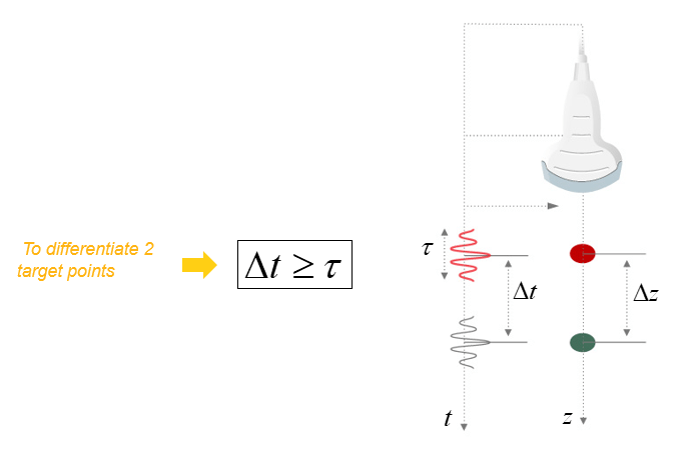

If we consider that an ultrasound wave propagates in the soft tissues at a constant mean speed c, the time t (echo flight time) that elapses between the emission and the reception of an echo, corresponds to the duration of a round trip to the target which is expressed simply by the fundamental relationship of ultrasound: ct = 2z, where c is the ultrasound speed, t is the time of propagation, and z is the penetration distance.

Axial Resolution

The Axial Resolution is the minimum distance that can be differentiated between two reflectors located parallel to the direction of the ultrasound beam.

Mathematically, it is equal to half the spatial pulse length.

However, the Axial resolution is limited by the duration of the ultrasonic pulse. It is high when the spatial pulse length is short.

The axial resolution or the resolution in the direction of the axis of the ultrasonic beam depends on the duration of the ultrasonic pulse.